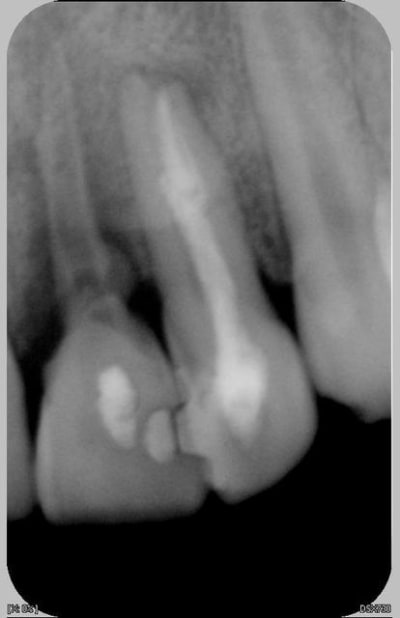

Suite du traitement

ouverture de la 11

nettoyage + EDTA-Hypochlorite sous ultrason

appareil provisoire sous le coude

la 11 n'est plus mobile

la patiente part pour deux mois, revient en septembre

la 21 au temps pour moi

hydroxyde de calcium dans le canal en attente

Il est évident que la 22 est à reprendre